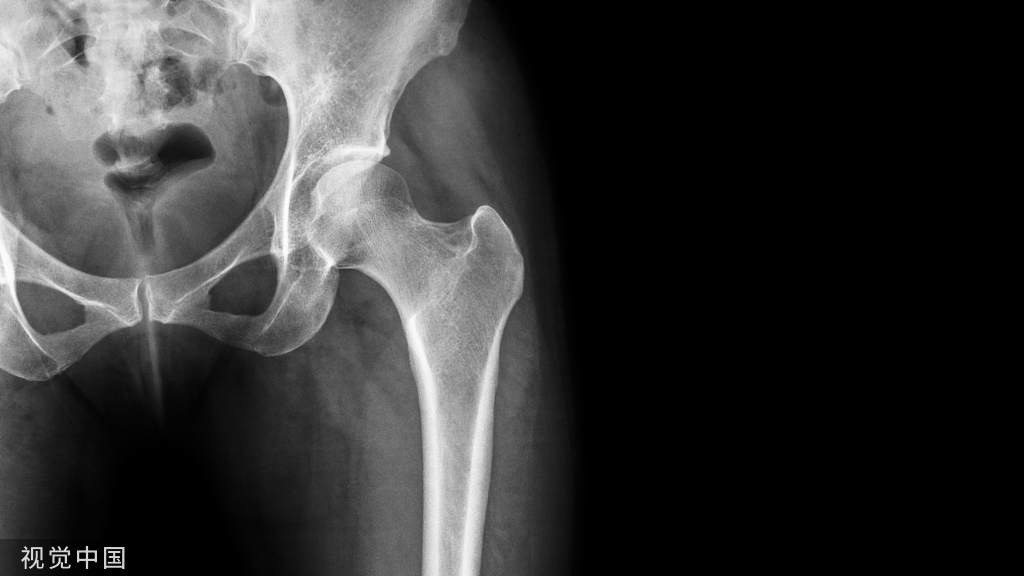

- 干骺端骨折:6-12 个月 取出

- 骨干板:12-18 个月 取出

- 髓内钉:8-24个月 取出

内固定取出后,造成的骨骼强度减弱 30% 或更多。据报道,1-3% 的患者在移除内固定后会发生再骨折。根据具体情况,必须建议患者在移除植入物后长达 12 周内避免承重或撞击。同样,过早取出可能导致早期再骨折